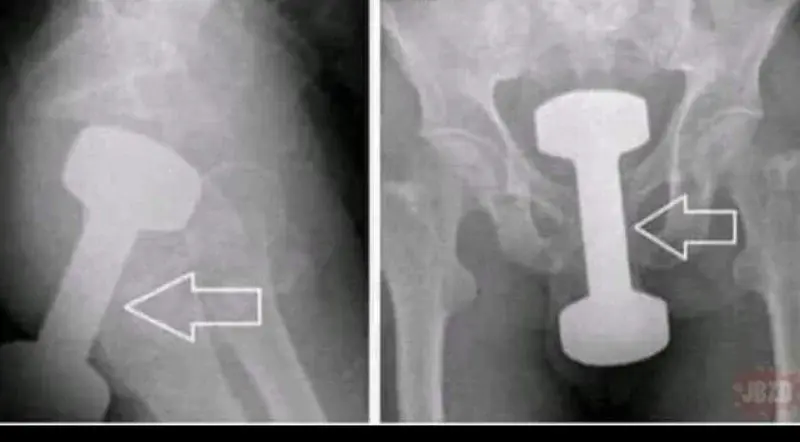

Wśród plusujących wylosuję jedną osobę która zgarnie taki zestaw jak na zdjęciu.